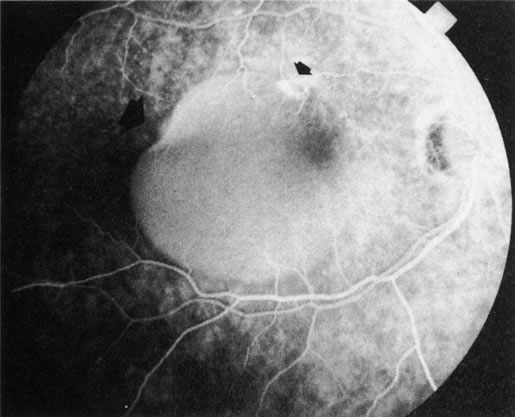

Clinically discernible peripheral dependent bullous neurosensory detachments have been described in patients with chronic CSC.85–92 Yannuzzi and co-workers first characterized the presence of RPE atrophic tracts extending inferiorly in the fundus periphery secondary to antecedent retinal detachment in patients with CSC.85 Presumably, there is a particularly severe and/or longstanding leakage of fluid from an RPE defect in the subretinal space at the posterior pole. The subretinal fluid gravitates inferiorly to form a dependent neurosensory detachment in a “flask,” “teardrop,” “dumbbell,” or “hourglass” pattern (Fig. 31). Sometimes the tract of subretinal fluid connecting the macular detachment with the bullous neurosensory detachment in the inferior hemisphere is so shallow that it is very difficult to appreciate. The RPE under the chronic retinal detachment experiences atrophic changes that appear as atrophic RPE tracts connecting the posterior pole with the dependent retinal detachment. The retina itself develops secondary manifestations including pigment migration, capillary dilatation (telangiectasia) proximally and capillary nonperfusion (ischemia) distally to the area of detached retina (see Fig. 31). The changes in the RPE consist of both RPE atrophy and pigment clumping in the form of perivascular deposits or bone spicules, a condition described by Gass as a “pseudoretinitis pigmentosa–like atypical CSC presentation.”87

Fig. 31. A 47-year-old woman with an18-year history of central serous chorioretinopathy in both eyes. A. Color photograph composite of the left eye shows bullous dependant detachment of the neurosensory retina inferiorly. B. Fluorescein angiogram composite reveals diffuse decompensation of the retinal pigment epithelium, multiple scattered pigment epithelium detachments 9PEDs), and obliteration of the retinal capillaries in the region of the detachments. Note the presence of early neovascularization at the junction between perfused and non-perfused retina. C. Clinical photograph of the left eye shows PED superior to the optic disc partially surrounded by fibrin deposits. D. Fluorescein angiography confirms the presence of active leakage from the serous PED. E, Color photograph composite of the same eye 2 months after laser treatment of the site of leakage reveals partial resolution of the detachment and lipid precipitation. F. Clinical photograph composite 16 months after the laser treatment in the area of the leakage shows complete resolution of the detachment and partial reperfusion of the inferior retina.